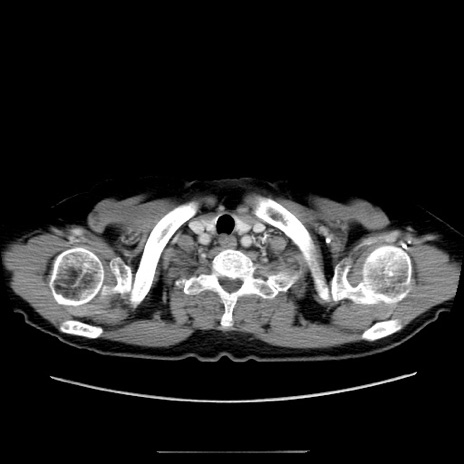

症例5(横断像)

【症例】70歳代女性

【主訴】お腹が張る

【現病歴】1週間くらい前から腹部膨満の自覚あり。昨日夜から増悪したため、本日救急外来受診。

【身体所見】意識清明、BT 36.5℃、BP 165/106mmHg、HR 80bpm、SpO2 98%、腹部:膨満、軟、自発痛・圧痛なし、触診にて不快感あり、腸蠕動音:減弱

【データ】WBC 12600、CRP 1.04